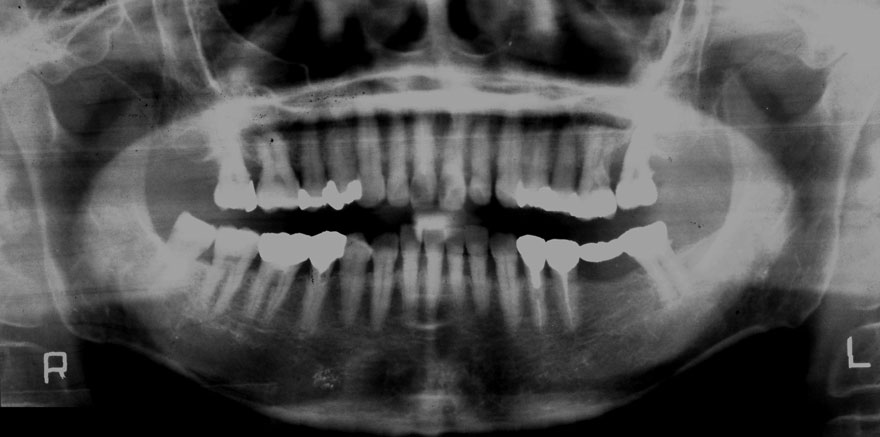

初診時 60歳 男性

29年後 89歳